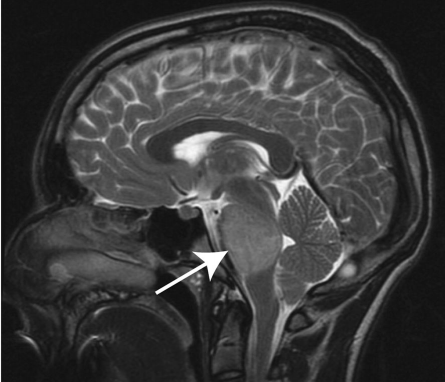

谁按下了快进键?让这个胶质瘤快速蔓延? 年过半百的李先生出现腿部发麻,腰痛,无法行走。经在当地医院检查后诊断为延髓肿瘤,医生认为这个位置手术风险太大,不建议手术。不到一个...